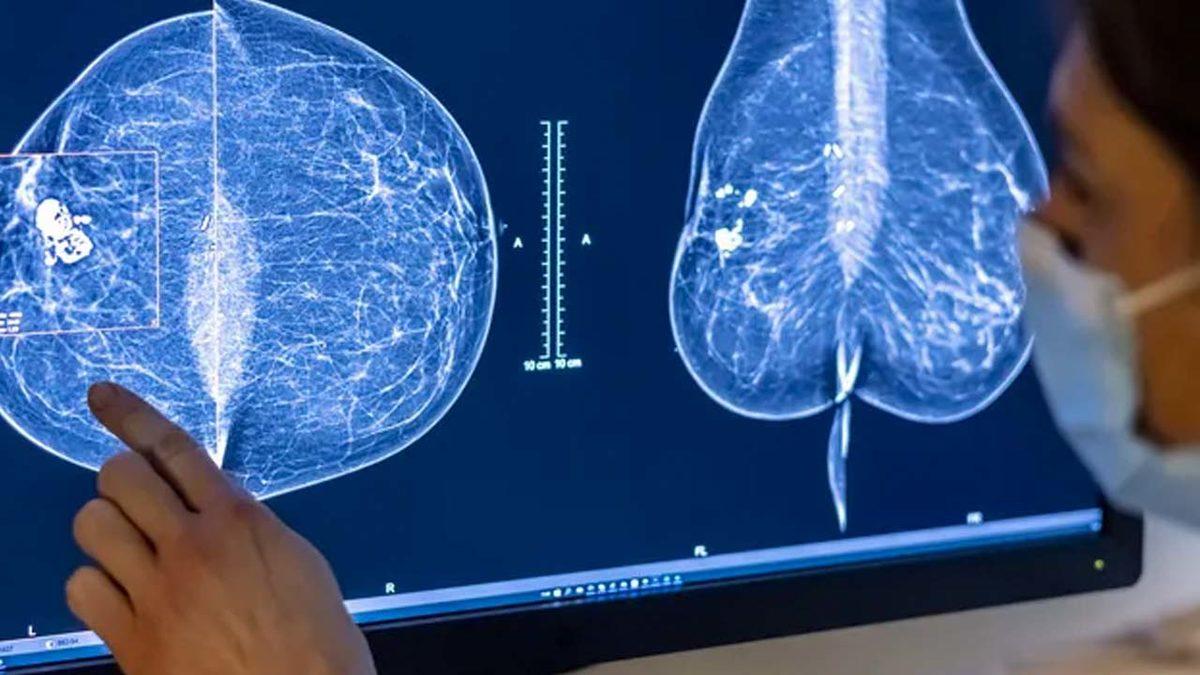

Bugün, bu ortaklıklar arasına bir yenisi daha katıldı. Şirket, medikal teknoloji şirketi iCAD ile iş birliğine imza attı. İş birliği kapsamında şirket, meme kanserinini tespitini ve risk değerlendirmesini çok daha kolaylaştıracak ve doğruluğunu artıracak yapay zekânın araştırma modelini iCAD’e lisansladı.

Google, iCAD’e lisansladığı yeni teknoloji üzerinde yıllardır çalışıyordu. 2020 yılında yayımladığı araştırmasında da geliştirdiği yapay zekânın meme kanseri tespitinde radyologlardan daha iyi performans gösterdiğini ortaya koymuştu. Öyle ki yapay zekâ, yanlış ‘negatif’ sonuçları %9,4; yanlış ‘pozitif’ sonuçları da %5,7 oranında azaltmıştı.

iCAD bünyesine geçen yeni yapay zekâ ise şirketin mevcut araçlarına entegre edilecek. Bunlardan birisi, şirketin “ProFound” yapay zekâsı olacak. Halihazırda 3D tomosentez mamografiyi analiz eden yapay zekâ, Google’ın araştırma modeliyle daha doğru sonuçlar sunabilecek.